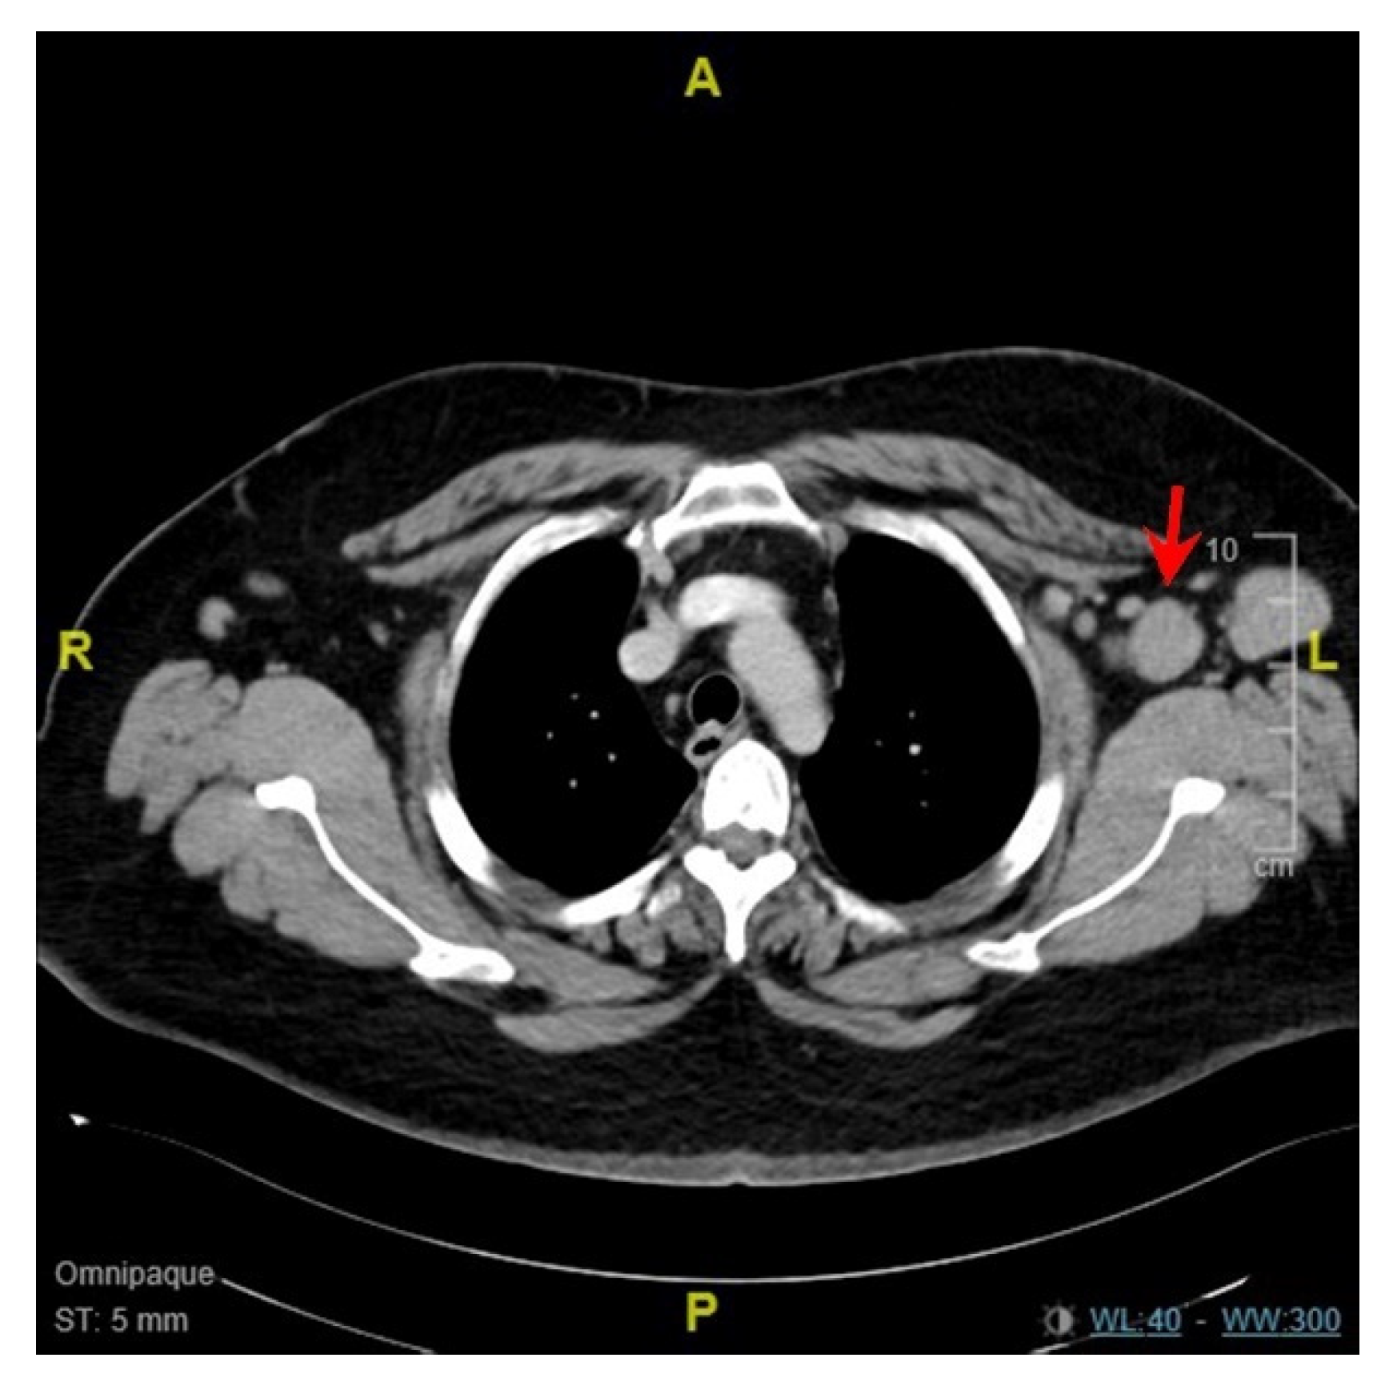

2. Case Report